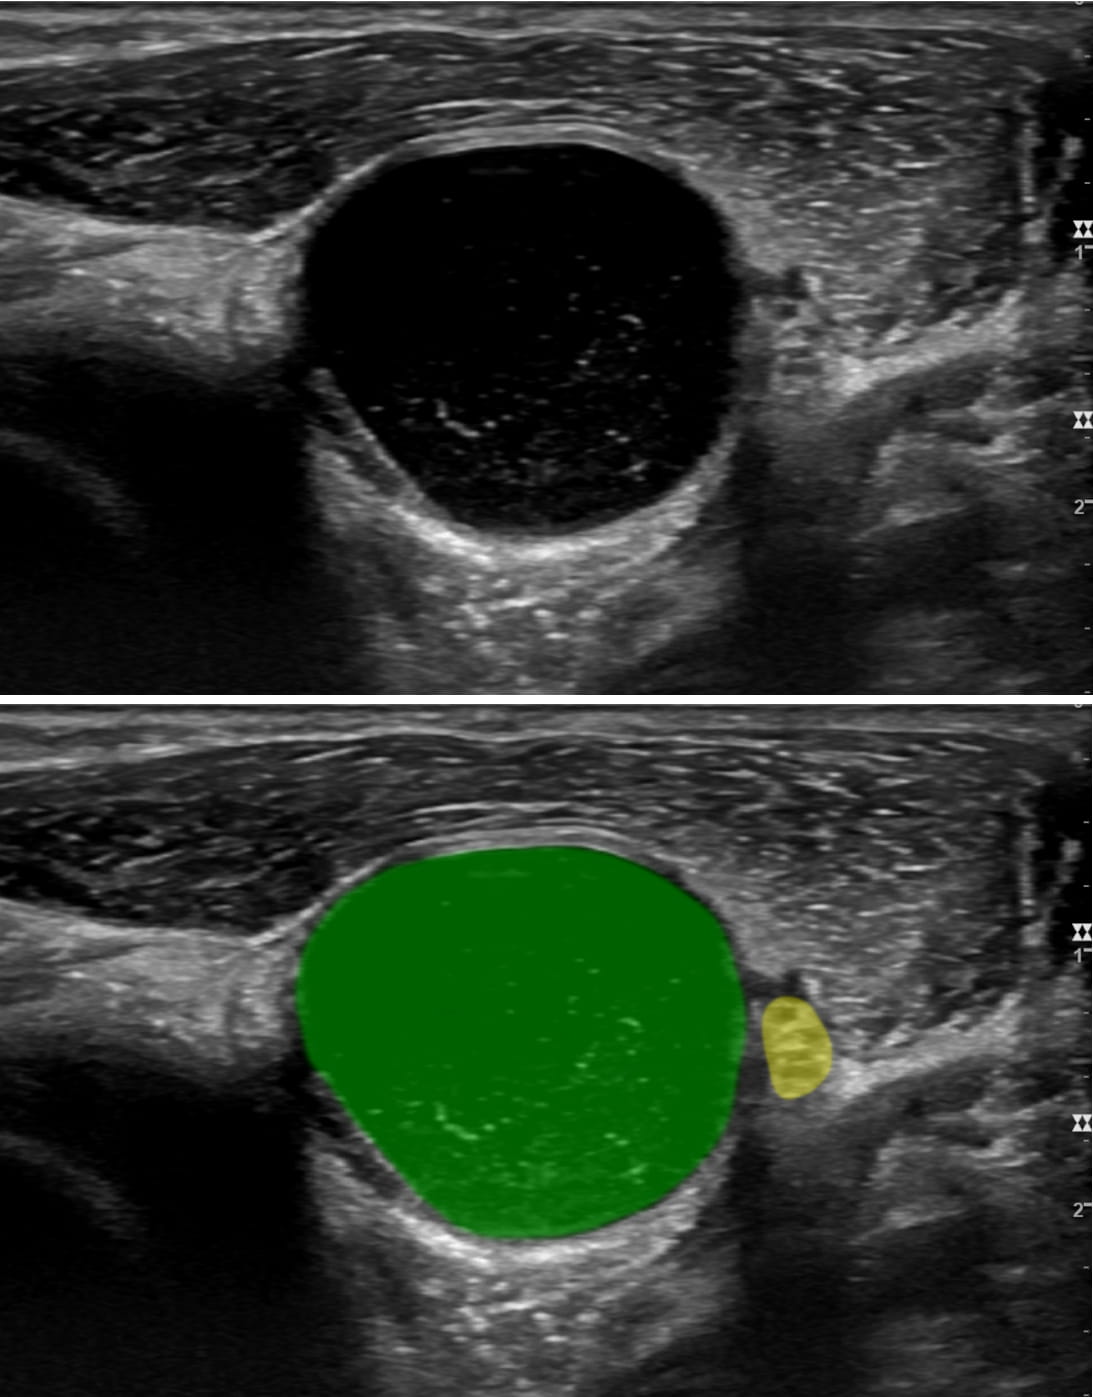

In another case, a woman presented with a complete wrist drop that emerged upon waking in the morning. She was unable to lift her fingers and had numbness of the back of her hand. An EMG study indicated that it was likely from compression, perhaps due to sleeping on it in an awkward position, a problem that would normally resolve on its own. However, a subsequent ultrasound identified a large synovial ganglion cyst in her upper arm, which was removed without delay.

“These are just two examples of how neuromuscular ultrasound adds valuable anatomical and pathological information to a diagnostic workup,” Dr. Preston says. “It has dramatically changed how we look at things.”